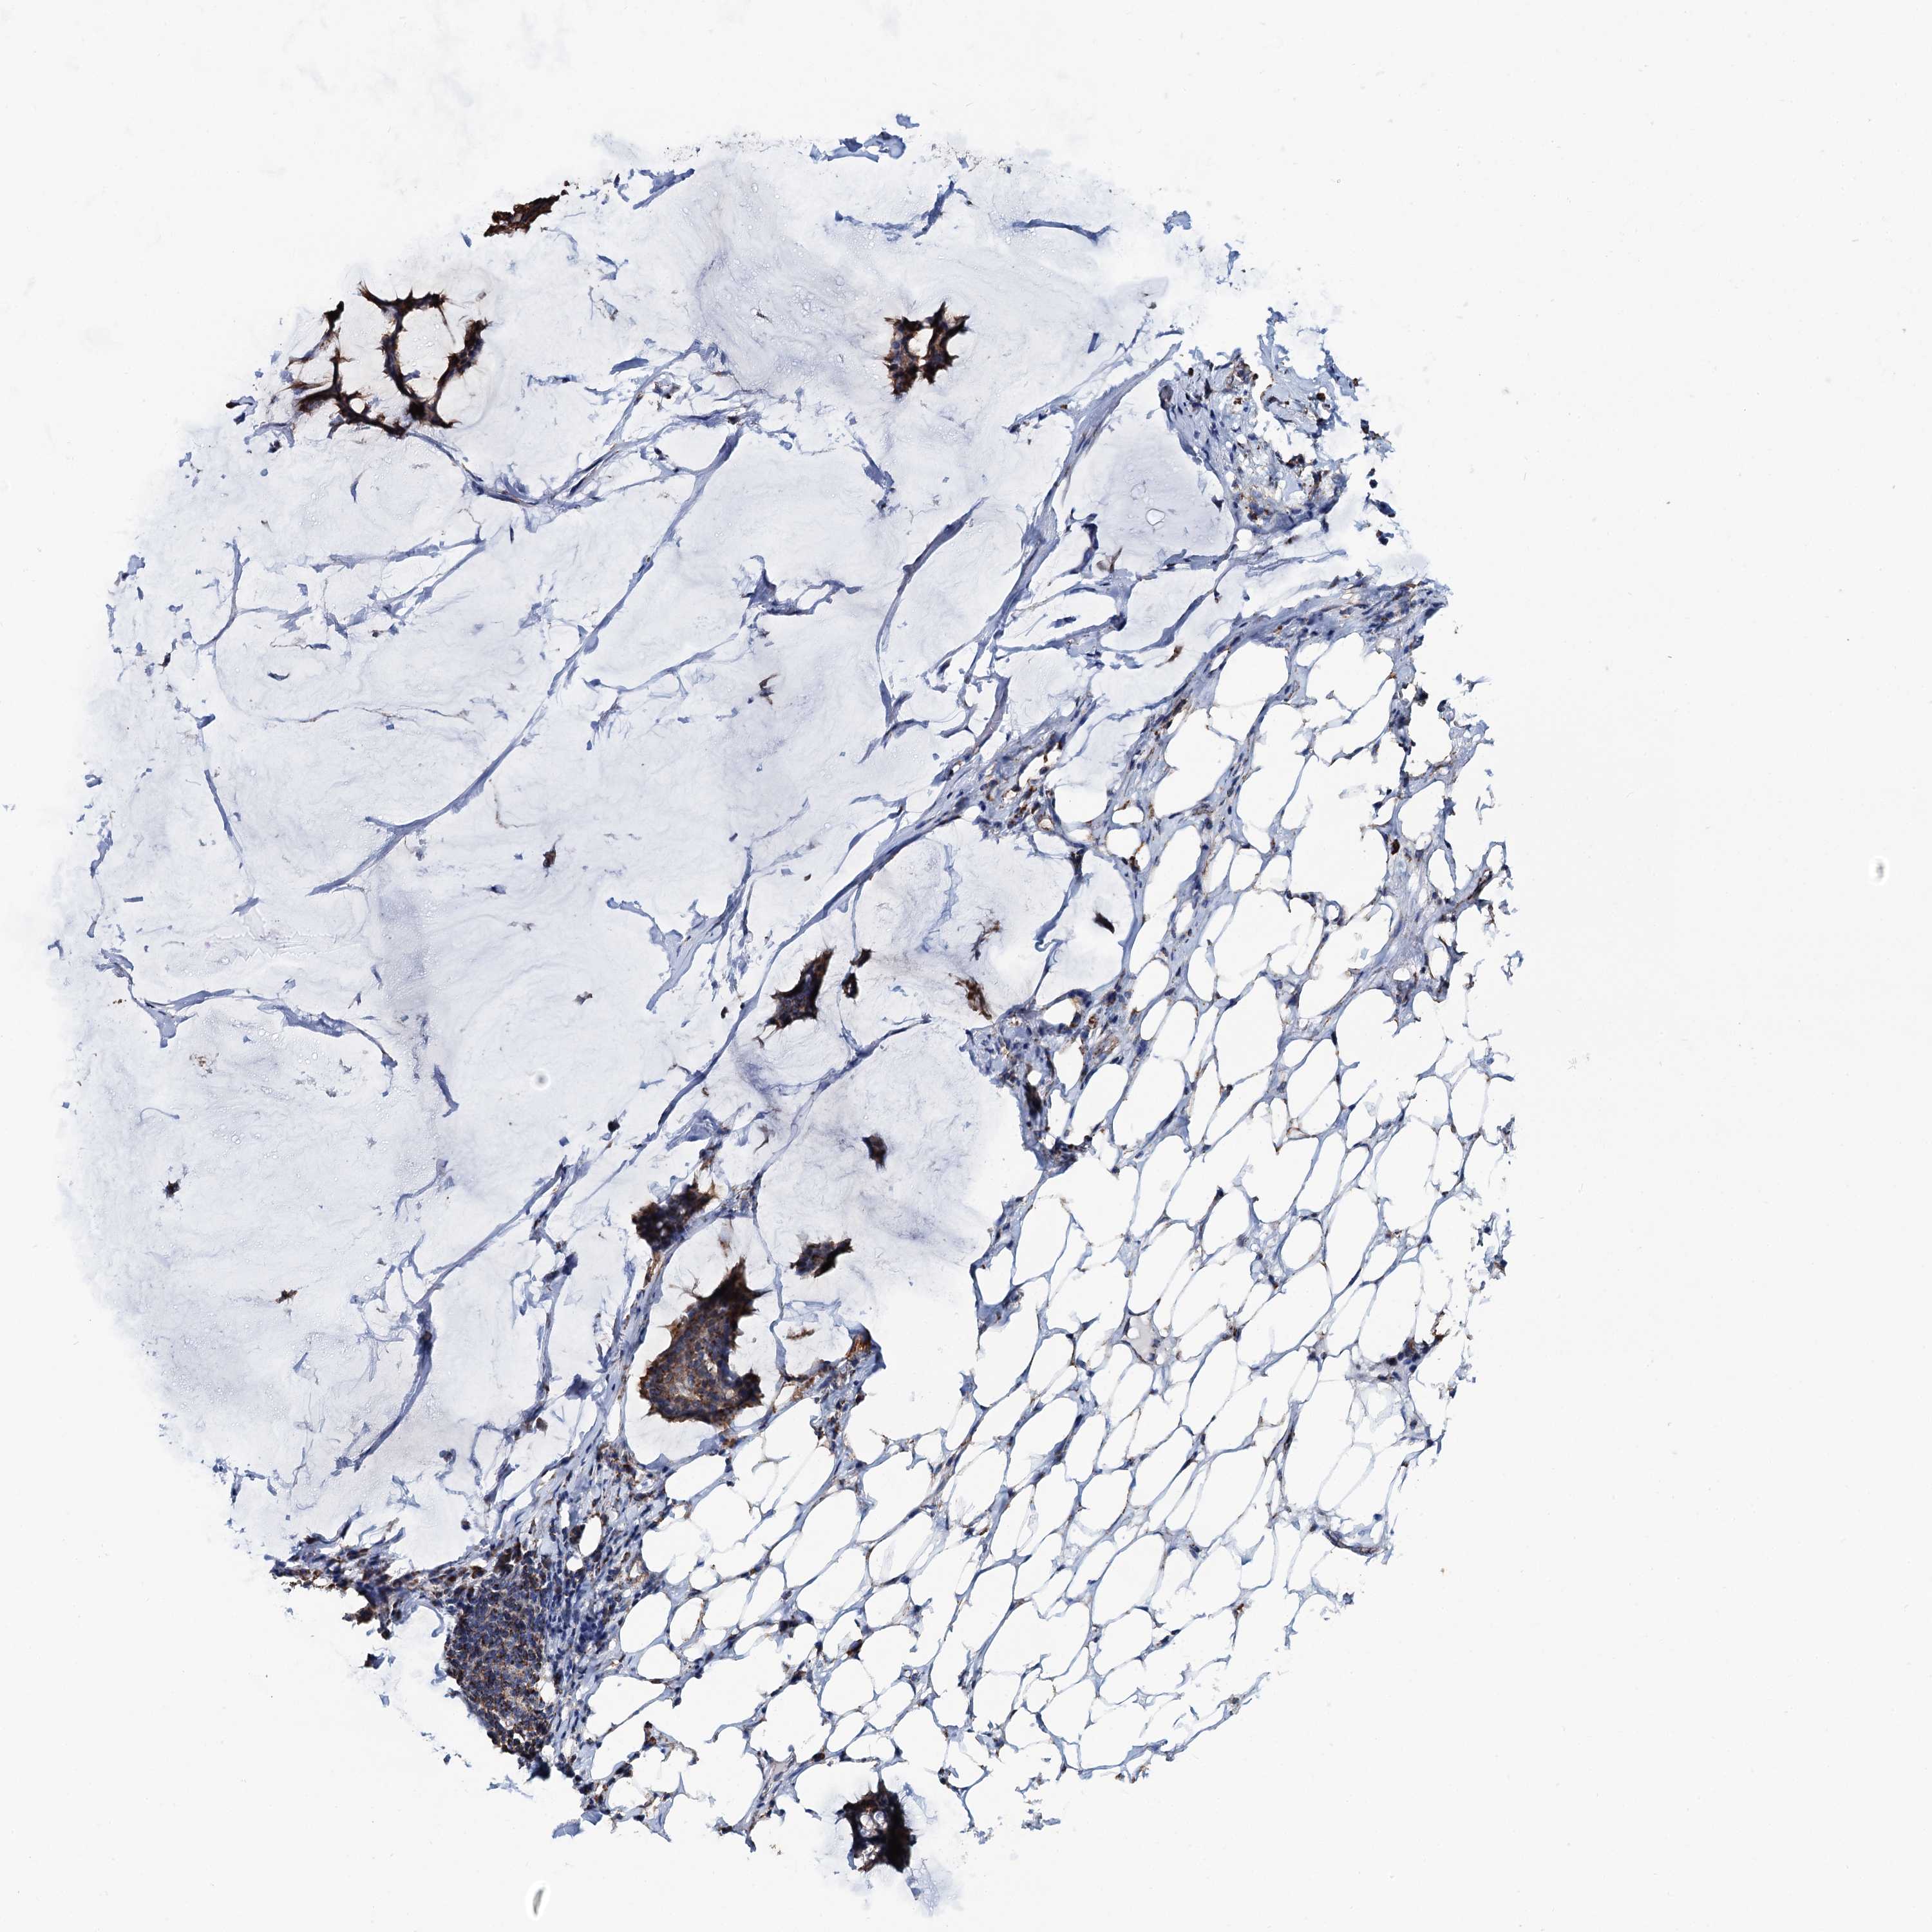

CANCER BREAST CANCER Show tissue menu

BRCA TCGA BRCA VALIDATION PROTEIN EXPRESSION